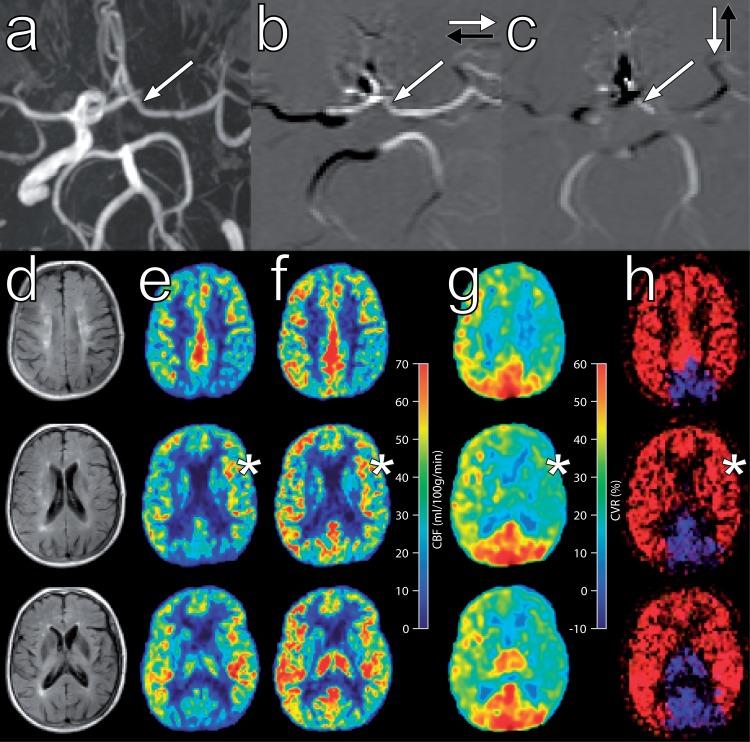

Collateral blood flow plays a pivotal role in steno-occlusive internal carotid artery (ICA) disease to prevent irreversible ischaemic damage. Our aim was to investigate the effect of carotid artery disease upon cerebral perfusion and cerebrovascular reactivity and whether haemodynamic impairment is influenced at brain tissue level by the existence of primary and/or secondary collateral. Eighty-eight patients with steno-occlusive ICA disease and 29 healthy controls underwent MR examination. The presence of collaterals was determined with time-of-flight, two-dimensional phase contrast MRA and territorial arterial spin labeling (ASL) imaging. Cerebral blood flow and cerebrovascular reactivity were assessed with ASL before and after acetazolamide. Cerebral haemodynamics were normal in asymptomatic ICA stenosis patients, as opposed to patients with ICA occlusion, in whom the haemodynamics in both hemispheres were compromised. Haemodynamic impairment in the affected brain region was always present in symptomatic patients. The degree of collateral blood flow was inversely correlated with haemodynamic impairment. Recruitment of secondary collaterals only occurred in symptomatic ICA occlusion patients. In conclusion, both CBF and cerebrovascular reactivity were found to be reduced in symptomatic patients with steno-occlusive ICA disease. The presence of collateral flow is associated with further haemodynamic impairment. Recruitment of secondary collaterals is associated with severe haemodynamic impairment.

侧支循环血流在狭窄性颈内动脉(ICA)疾病中起着关键作用,可防止不可逆的缺血性损伤。我们的目的是研究颈动脉疾病对脑灌注和脑血管反应性的影响,以及原发性和/或继发性侧支循环的存在是否会影响脑实质水平的血液动力学。88 例狭窄性 ICA 疾病患者和 29 例健康对照者接受了磁共振检查。通过时间飞跃、二维相位对比 MRA 和区域性动脉自旋标记(ASL)成像确定侧支的存在。在乙酰唑胺前后用 ASL 评估脑血流和脑血管反应性。与 ICA 闭塞患者相比,无症状 ICA 狭窄患者的脑血流动力学正常,而 ICA 闭塞患者的两个半球的血流动力学都受到影响。在有症状的患者中,受累脑区的血液动力学始终存在损害。侧支循环血流的程度与血液动力学损害呈负相关。仅在有症状的 ICA 闭塞患者中募集继发性侧支循环。总之,在狭窄性 ICA 疾病有症状的患者中,CBF 和脑血管反应性均降低。侧支循环血流的存在与进一步的血液动力学损害有关。继发性侧支循环的募集与严重的血液动力学损害有关。